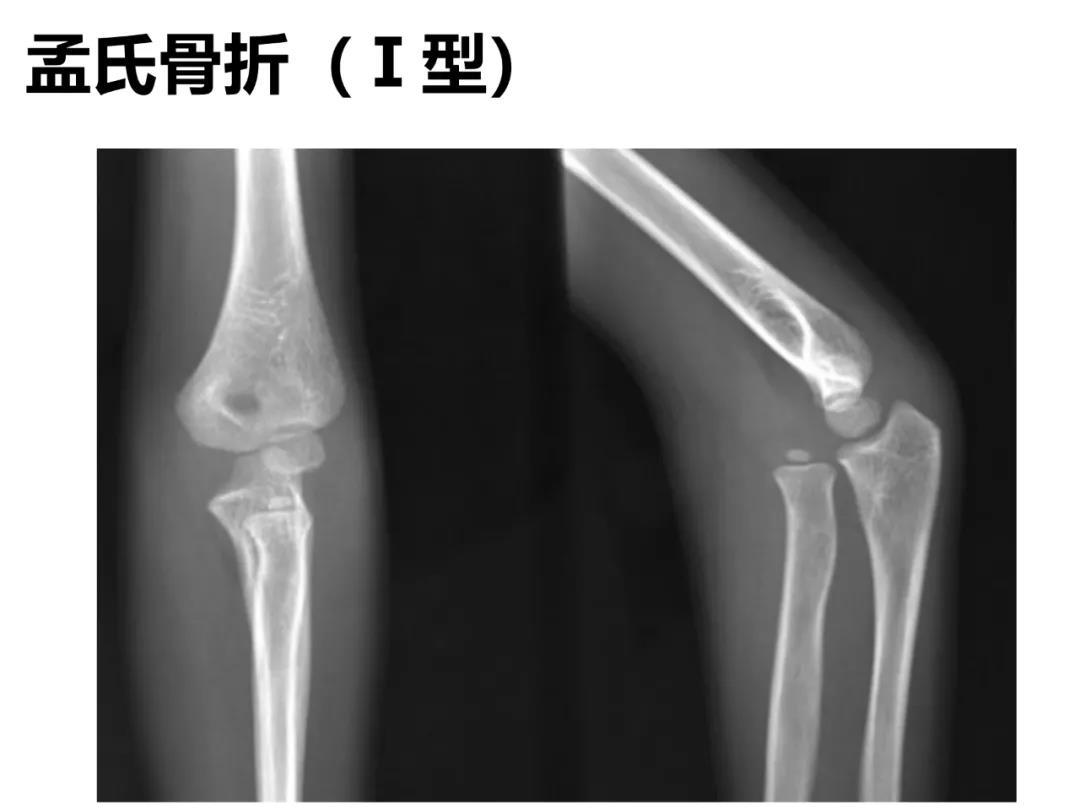

小儿骨科X线片汇总,临床读片宝典!